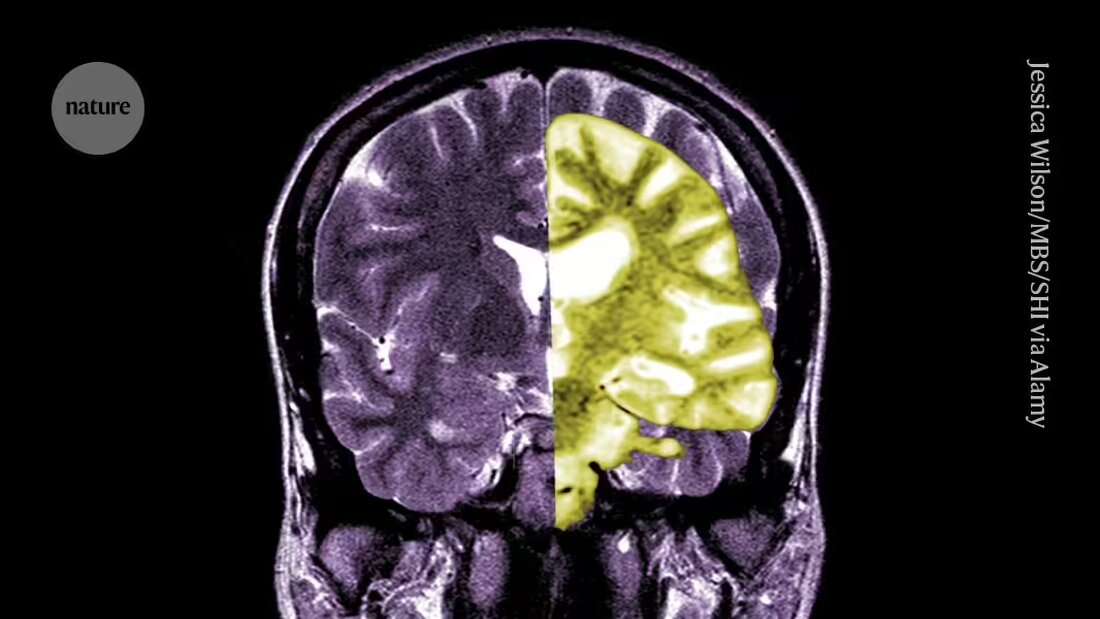

Lecanemab oder Leqembi ist ein monoklonaler Antikörper, der Amyloid, eine Substanz, die sich in den Gehirnen von Menschen mit Alzheimer zu toxischen Klumpen zusammenballt, beseitigt. Das Medikament, hergestellt von Eisai in Tokio und Biogen in Cambridge, Massachusetts, ist auch in China, Japan, Südkorea und den Vereinigten Arabischen Emiraten zugelassen.

Andere begrüßen die EMA und sagen, dass das Medikament zwar effektiv die Amyloidwerte im Gehirn gesenkt hat, ob die daraus resultierende Reduktion des kognitiven Abbaus zu klinisch relevanten Vorteilen für die Patienten führen wird, bleibt unklar. Sie geben an, dass die Möglichkeit schwerwiegender Komplikationen wie Blutungen oder Schwellungen im Gehirn, verursacht durch eine Nebenwirkung namens amyloidbezogene Bildgebungseffekte (ARIA), obwohl gering, eine große Sorge darstellt. „Eine vernünftige Bewertung der Risiken im Vergleich zu den Vorteilen dieses Medikaments sollte die Menschen dazu bringen, sehr skeptisch zu sein“, sagt Matthew Schrag, Neurologe an der Vanderbilt University in Nashville, Tennessee.